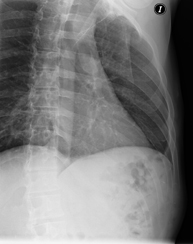

- Tórax

- RX Tórax

Técnica mediante la cual, utilizando rayos X, se obtienen imágenes de la caja torácica (corazón, pulmones, arcos costales, clavículas, etc.) para su estudio. - RX Esternón

Técnica mediante la cual, utilizando rayos X, se obtienen imágenes de la columna dorsal para su estudio. Indicaciones: traumatismo, dolor, escoliosis. - Esófagograma